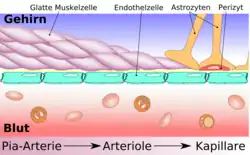

Diese besondere Abgrenzung des Bluts (intravasal) vom extravasalen Raum in Gehirn und Rückenmark ist bei allen Landwirbeltieren (Tetrapoda) ausgebildet und ermöglicht es, für das Nervengewebe eigene Milieubedingungen aufrechtzuerhalten (Homöostase). Im Wesentlichen wird diese Barriere von Endothelzellen gebildet, die hier in den kapillaren Blutgefäßen über Tight Junctions eng miteinander verknüpft sind.

Das wesentliche Element der Blut-Hirn-Schranke bilden die Endothelzellen mit ihren Tight Junctions. Für Funktion sowie Aufbau und Entwicklung der Blut-Hirn-Schranke sind jedoch noch zwei andere Zelltypen, die Perizyten und die Astrozyten, von großer Bedeutung.[1] Die Zell-Zell-Interaktionen zwischen Endothelzellen, Perizyten und Astrozyten sind so eng wie bei sonst keinen anderen Zellen. Diese drei Zelltypen zusammen bilden die Blut-Hirn-Schranke der meisten Wirbeltiere, die endotheliale Blut-Hirn-Schranke.[5][6] Die nachfolgenden anatomischen Angaben beziehen sich auf die endotheliale Blut-Hirn-Schranke der Wirbeltiere. Die bei einigen Wirbeltieren und vielen Wirbellosen ausgebildete gliale Blut-Hirn-Schranke wird am Ende dieses Kapitels gesondert aufgeführt.

Die Kapillargefäße werden – wie in den peripheren Blutgefäßen auch – von Endothelzellen gebildet. Das Endothel peripherer Kapillaren hat, für den Austausch von Wasser und darin gelösten oder suspendierten Stoffen zwischen dem Blut und der extrazellulären Flüssigkeit des umliegenden Gewebes, Öffnungen (Fenestrierungen) von ca. 50 nm Durchmesser und Zwischenzellspalten von 0,1 bis 1 µm Weite. Zwischen den Endothelzellen im Gehirn gibt es dagegen keine Fenestrierungen und keine Intrazellularspalten,[7] weshalb man auch von einem kontinuierlichen Endothel spricht.[8] Die dem Innenraum der Kapillare zugewandte (luminale) Membran unterscheidet sich bezüglich der Art der Membranproteine erheblich von der dem Interstitium zugewandten apikalen Seite.

Astrozyten sind sternförmig verzweigte, im Vergleich zu den Perizyten deutlich größere Zellen aus der Familie der Makroglia. Sie werden dem Zentralen Nervensystem zugerechnet und sind nach der Geburt noch teilungsfähig. Bei höheren Wirbeltieren haben sie keine direkte Schrankenfunktion, auch wenn sie die Kapillargefäße im Gehirn zu etwa 99 % mit ihren Endfüßchen bedecken.[6][53] Sie stehen allerdings in unmittelbarer Wechselwirkung mit den Endothelien.[54] Astrozyten induzieren in den Endothelien der zerebralen Blutgefäße die Funktion der Blut-Hirn-Schranke. Dies wurde durch Transplantationsversuche nachgewiesen. Zerebrale Blutgefäße, die in periphere Organe verpflanzt wurden, verhielten sich wie die dort vorhandenen „normalen“ Kapillaren und bildeten beispielsweise Fenestrierungen aus. Im umgekehrten Versuch nahmen periphere Kapillaren, die in das Zentralnervensystem verpflanzt wurden, den dortigen Phänotyp mit Tight Junctions an.[1][55] Auch in In-vitro-Versuchen zeigt sich der Einfluss der Astrozyten auf die Phänotypausprägung der Endothelien. In Co-Kulturen aus Astrozyten und Endothelzellen weisen die Endothelien eine höhere Dichtigkeit auf als in reinen Endothelkulturen.[56]

Astrozyten schütten eine Reihe von Botenstoffen aus, die die Durchlässigkeit des Endothels im Sekunden- bis Minutenbereich modulieren können.[57] Umgekehrt schütten die Endothelzellen den Leukämieinhibierenden Faktor (LIF), ein Zytokin der Interleukin-6-Klasse, aus, der die Differenzierung der Astrozyten induziert.[57] Der Abstand der Astrozytenfüßchen zu den Endothelzellen und den Perizyten beträgt nur 20 nm.[6][58]

Die Endfüßchen der Astrozyten bilden einen filigranen rosettenartigen Kontakt zu den Endothelzellen. Diese Anordnung ist für die wechselseitige Beeinflussung und Kommunikation der beiden Zelltypen wichtig. So ist zudem eine freie Diffusion zwischen dem Endothel und dem Parenchym des Gehirns möglich.[57]

Ein Netz von über 100 Milliarden Kapillargefäßen, deren Gesamtlänge bei einem Erwachsenen ungefähr 600 km beträgt, durchzieht das gesamte Gehirn.[21] Der durchschnittliche Abstand dieser Blutgefäße beträgt 40 µm.[63] Die unterschiedlichen Hirnregionen werden unterschiedlich stark versorgt. Die Dichte an Kapillargefäßen ist in der Großhirnrinde (Cortex cerebri) mit 300 bis 800 Kapillarquerschnitten pro mm² Gewebe am höchsten.[1]

Die Gesamtfläche der Blutgefäße im Gehirn liegt zwischen 12[64] und 20 m².[65] Etwa 610 ml Blut fließen pro Minute durch diese Gefäße, wobei die mittlere Strömungsgeschwindigkeit bei 1 mm/s liegt. Der mittlere Blutdruck ist dabei im Bereich von 15 bis 35 mmHg.[3] Die mittlere Passagezeit (mean transit time MTT) beträgt 5 Sekunden. Im Vergleich dazu liegt sie im Darm, dessen Blutgefäße eine Oberfläche von 180 m² aufweisen, bei etwa 40 Stunden[66][67] und in der Leber – mit 70 m² – bei 30 Sekunden.[68][69][70]